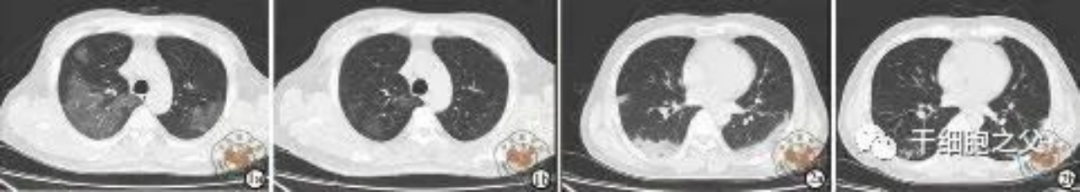

如圖所示,1a-1b:細(xì)胞輸注后,炎癥指標(biāo)改善,復(fù)查胸部CT提示雙肺病灶較前吸收,呼吸道癥狀改善,新型冠狀病毒核酸檢測連續(xù)2次陰性,治愈出院。圖2a-2b:2次干細(xì)胞輸注后炎癥指標(biāo)改善,復(fù)查時(shí)氧合指數(shù)升高至301 mmHg,胸部CT提示雙肺病灶較前吸收,患者呼吸道癥狀改善,新型冠狀病毒核酸檢測連續(xù)2次陰性,治愈出院。